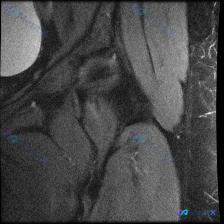

看到一份髋关节MRI T1序列冠状位的病例材料,用户预设想了解盂唇病变的可能性。 先看基础影像分析: - 扫描范围:单侧髋关节区域,包括股骨头、股骨颈、大转子、髋臼及其关节间隙 - T1序列特征:正常骨髓高信号,皮质骨低信号,肌肉中等信号,关节软骨及韧带清晰 - 股骨头/股骨颈:轮廓光滑,未见水肿、...

看到一个髋关节MRI病例,先给大家分享一下核心发现: 影像类型:髋关节MRI冠状位T1加权成像 主要表现:股骨头及股骨颈近端骨髓呈弥漫性T1低信号,与正常脂肪骨髓的高信号形成鲜明对比;髋臼顶轮廓清晰,关节间隙无明显狭窄,盂唇在T1序列上未见明确撕裂征象。 患者主诉提到了“盂唇病变”,但影像核心是骨髓...

最近看到一个髋关节病例,临床怀疑盂唇病变,但提供的单张MRI-T1冠状位影像未发现明确异常。影像显示股骨头形态基本圆滑,与髋臼窝对合良好,骨髓信号均匀,未见明显的骨髓异常或结构破坏。 大家来讨论一下: 1. 这种情况下还需要做哪些检查来明确诊断? 2. 可能的诊断方向有哪些? 3. 单序列MRI的局...

整理到一个髋关节MRI分析的内容,仅提供了单张T1序列冠状位图像,临床关注点是盂唇病变。先看一下这张图像的客观描述: 骨骼结构:股骨头圆形,轮廓光整,骨皮质连续,骨髓信号均匀;髋臼形态连续,骨皮质清晰;大转子区域骨皮质完整。 关节间隙:宽度基本对称,无明显狭窄,无异常信号填充。 软骨与盂唇:股骨头表...

整理到一张髋关节T1加权冠状位MRI的病例资料,初始有人提问「能否观察到盂唇病变」。先放这张图的核心影像描述:图像聚焦一侧髋关节,股骨头形态基本呈圆形,股骨头前上方负重区皮质下可见清晰带状低信号影,其余股骨头、颈骨髓信号为正常脂肪高信号,关节囊无明显增厚或积液。 想问问大家:仅看这张图的描述,您第一...